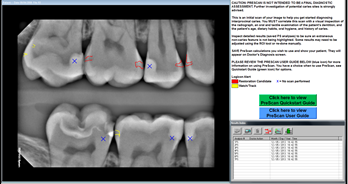

Logicon Software 5.1

From Carestream Dental comes Logicon software, a computer-aided diagnostic tool. This is not a hand-held device. It uses a database of histologically validated caries cases to help determine whether caries are present.

According to Carestream, Logicon Software version 5.1 is clinically proven to help dentists find up to 20 percent more interproximal caries on permanent teeth than traditional methods, and is the only commercially available FDA-approved computer-aided radiographic caries diagnosis software. Latest software improvements further enhance the detection process. With a few clicks, Logicon Caries Detector PreScan applies the algorithm on all eligible inter-proximal surfaces within a radiograph to generate a view of existing caries, helping the dentist verify manual findings by focusing on surfaces that require further investigation.

Logicon software operates only within the confines of Carestream Dental Imaging software. It cannot be integrated with any other dental imaging software.